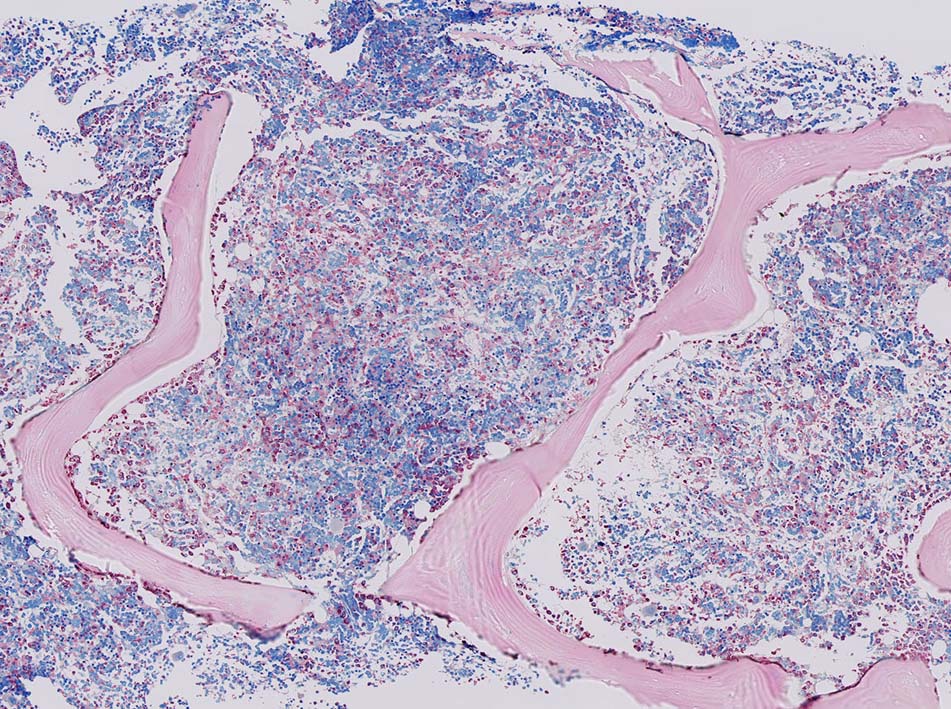

• 肝, 脾, 骨髄では類洞ないし静脈洞浸潤が顕著。脾臓では赤脾髄領域を中心に拡張した静脈洞内に腫瘍細胞が浸潤する。

• 肝臓では門脈域は通常保たれる。脾臓では白脾髄は通常保たれている。

骨髄浸潤所見

同じ患者さんの骨髄所見です. (サムネイルのクリックで大きな画像が見られます.)

骨髄への腫瘍細胞浸潤はintertrabecular patternで, 腫瘍細胞は小集簇巣を形成して散在性に認められた. HE, ASD-Giemsaのみでの浸潤, 増殖の確定はなかなか難しいようです.

ASD-GiemsaではASDに染まらない(陰性の)あやしい細胞塊があるように見える. 細胞小塊はCD3陽性.

骨髄クロットでは, 十分量が採取されているにもかかわらず, CD3陽性細胞は微小な集簇巣が2個ほど認められるのみであとは散在している.

免疫染色でCD3陽性となる細胞集塊のASD-Giemsa像. 肝類洞内浸潤細胞に比較して核, 細胞が紡錘形の傾向を示している.